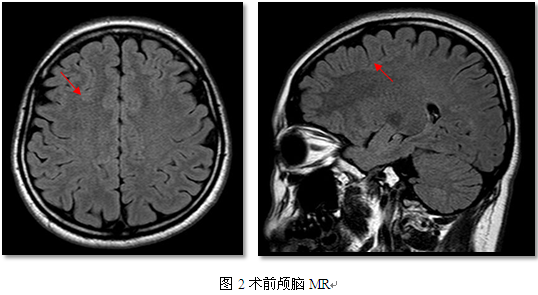

小徐经过多种药物治疗,但疗效欠佳,考虑药物难治性癫痫。入院后完善相关检查:视频脑电图,间歇期可见右侧脑区癫痫样放电,额区著;临床发作:过度运动→ 恐惧→发作后咳嗽(2/7)。EEG无侧向性。头磁共振:右侧中央前沟皮层可疑增厚。颅脑PET-CT:右侧额叶局灶性低代谢。

I期评估,考虑致痫灶位于右侧中央前沟附近,邻近中央前回,直接一次手术切除,需要扩大切除范围,术后可能出现左侧肢体偏瘫,建议先行颅内电极置入,明确致痫灶范围及与功能区(中央前回)的关系。待II期评估后,明确放电范围,及其致痫灶与中央前回的关系,在行手术治疗切除致痫灶。